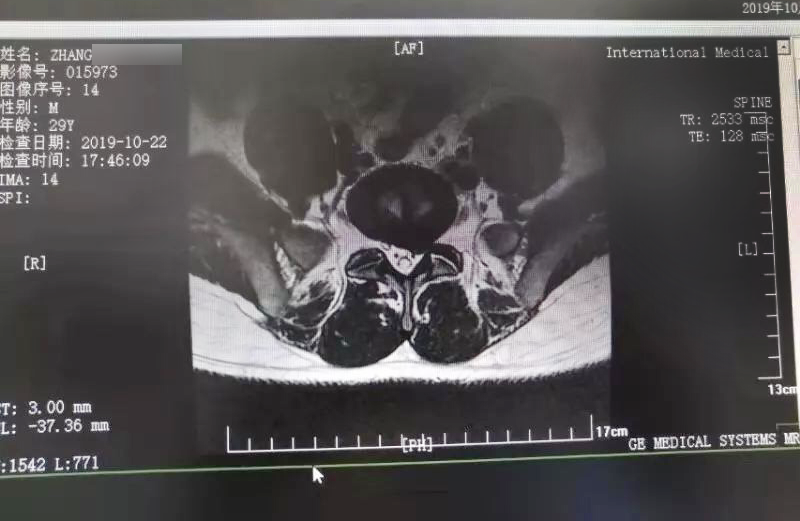

三秦網(wǎng)報(bào)道—西安國(guó)際醫(yī)學(xué)中心骨科醫(yī)院成功完成首例椎間孔鏡手術(shù)

三秦網(wǎng)報(bào)道—西安國(guó)際醫(yī)學(xué)中心骨科醫(yī)院成功完成首例椎間孔鏡手術(shù)。點(diǎn)擊閱讀